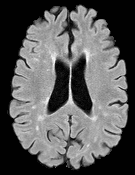

Patch size is another important parameter of the network. In computer vision applications such as object detection, usually a whole 2D image is used as a feature. However, full 3D medical images can not typically be used because of memory limitations. Fig. 4 shows examples of lesion memberships obtained with different sized 2D patches. As the patch sizes increases, the false positives that are mostly observed in the cortex tend to decrease. Fig. 5 shows a plot of Dice and LFPR with various patch sizes, ordered from left to right according to their increasing size. Note that smaller patches ( to ) produced significantly lower Dice and higher LFPR compared to other patches (), as seen from the memberships in Fig. 4. Also some of the highest Dice and lowest LFPR were observed for patches with large in-plane size, i.e., , , and . It was observed in Fig. 5 that there is no significant difference between Dice coefficients for , , or , but LFPR of both and are significantly lower than that of (). We chose as the optimal patch size. Other choices of smaller and patches (not shown) yielded worse results. Note that although training was performed with different patch sizes, the memberships were generated slice by slice, as the trained model consisted only of convolutions and did not need any information about patch sizes.